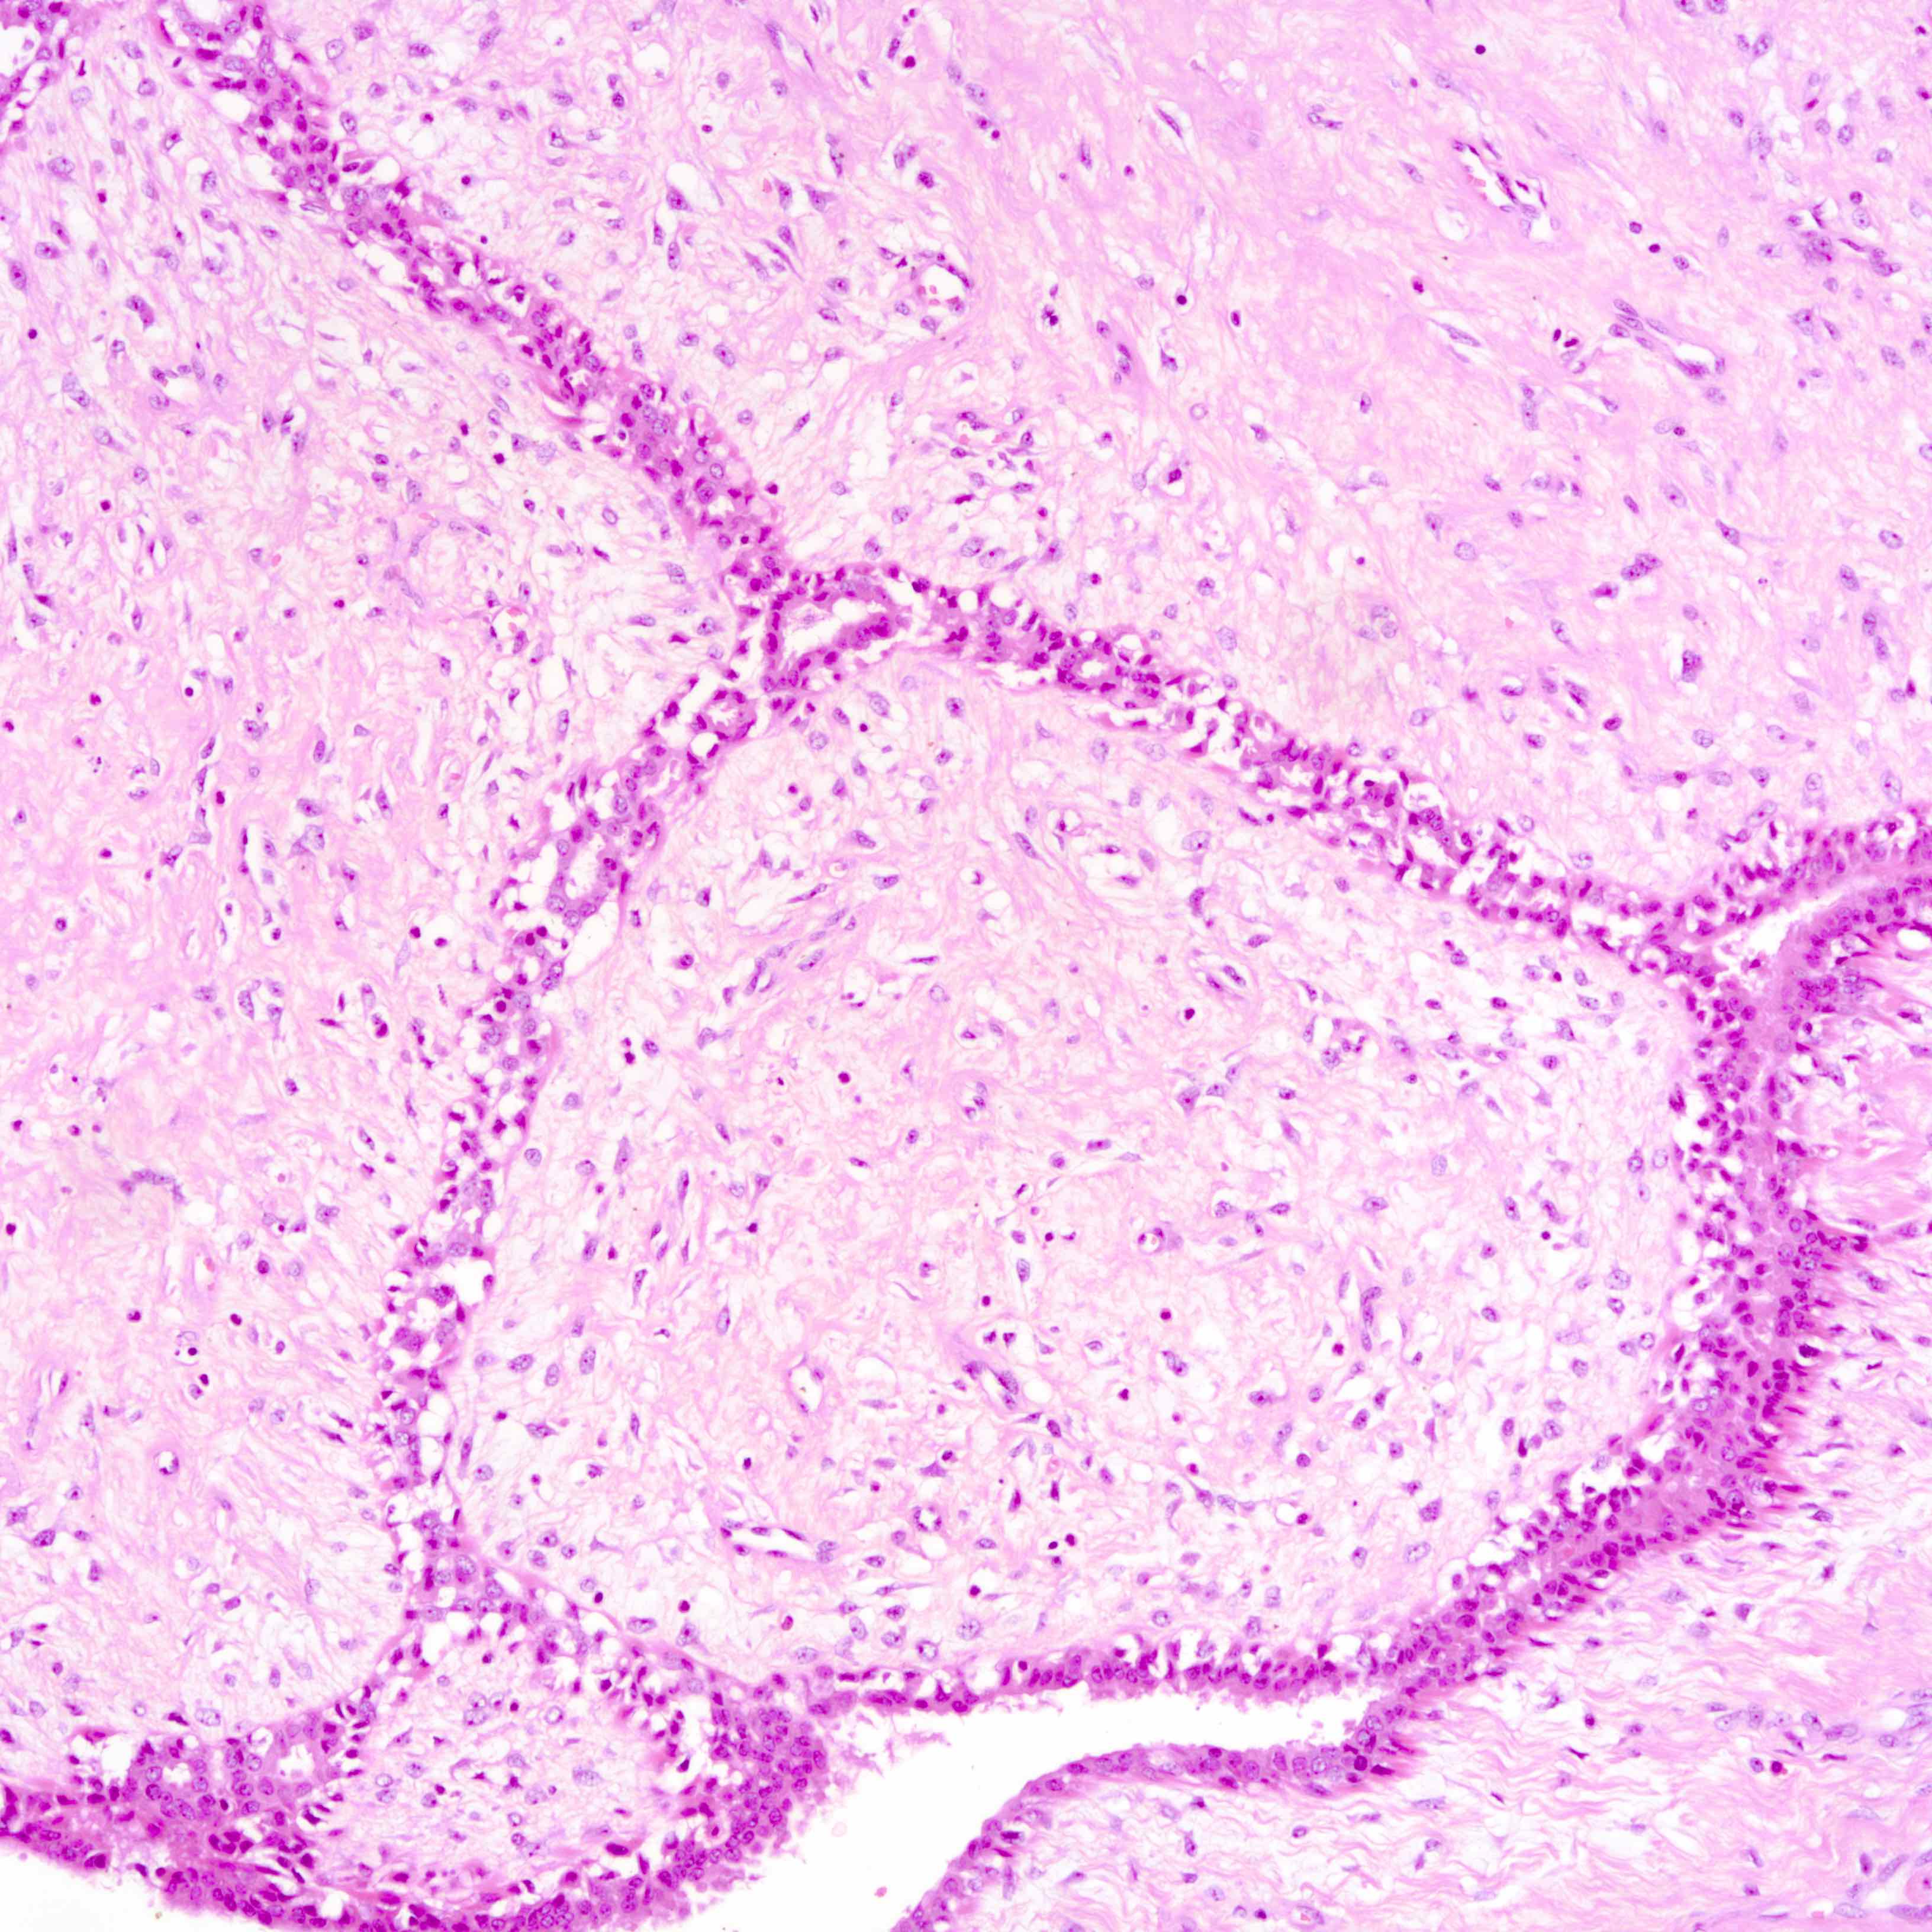

Microscopic (histologic) images

Contributed by Joshua J.X. Li, M.B.Ch.B. and Gary M. Tse, M.B.B.S.

Benign phyllodes tumor

Borderline phyllodes tumor

Malignant phyllodes tumor